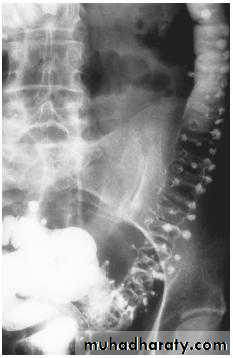

Signs of Crohn disease on barium studies include:

• Ulcers (rose-thorn ulcers or deep fissures).

• Strictures (string sign).• Intestinal obstruction.

• ‘Cobblestoning’ due to fissures separating islands of intact mucosa

• Segmental distribution: diseased segments separated by normal bowel

• Separation of loops of bowel due to bowel wall thickening or an inflammatory mass

• When involved the cecum is usually contracted.

• The rectum is often spared

• Ileocecal valve is normal or narrowed; terminal ileum stenosed.

• Fistula to other loops of small bowel, colon, bladder or vagina